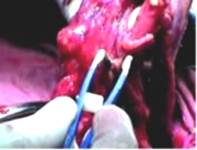

В Институте электросварки им. Е.О. Патона НАН Украины определены условия образования сварного соединений ткани токами высокой частоты и разработан удовлетворяющий этим требованиям сварочный комплекс, в состав которого входит энергетический блок, состоящий из источника питания (высокочастотного коагулятора) с системой управления и специально созданным для этой цели программным обеспечением, подсоединяемых к источнику питанния биполярных сварочных медицинских инструментов (пинцетов, зажимов и лапораскопов) и специальных сборочных приспособлений. Система управления процессом сварки действует на основе обратных связей.

• с помощью биполярного сварочного пинцета достигается соединение продольных разрезов серозной и подслизистой оболочек, мышечной ткани участка толстой кишки точечным сварным швом с достижением полной герметичности;

• достигается формирование циркулярного анастомоза толстой кишки наложением однорядного серосерозного сварного шва. Полная герметичность сварного шва подтверждается послеоперационным вскрытием через три месяца после эксперимента. При этом место наложения сварного шва определяется с трудом;

• достигается герметичное сварное соединение продольного разреза желчного пузыря. С помощью сварочного биполярного пинцета формировался точечный сварной шов длиной 6-7 мм.